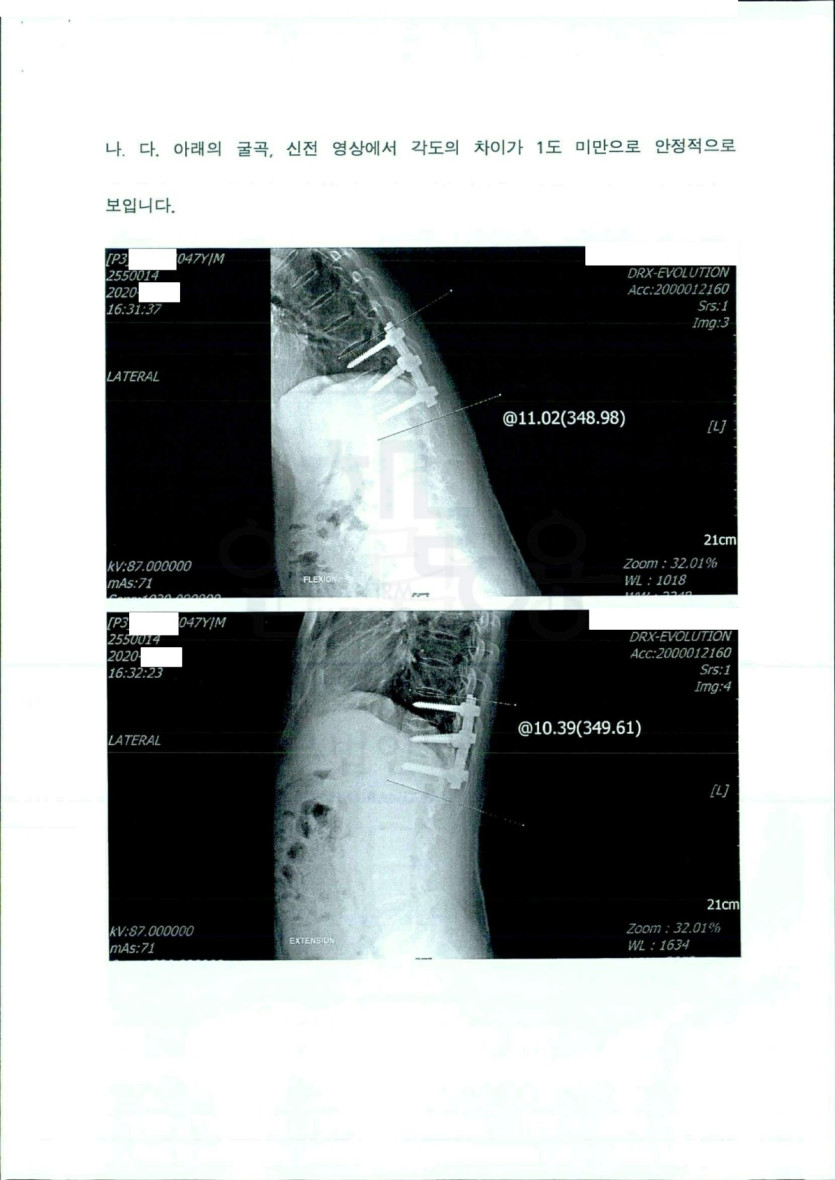

​제 7 경추 및 제 12 흉추 추체 골절

1, 2 요추 횡돌기 골절​